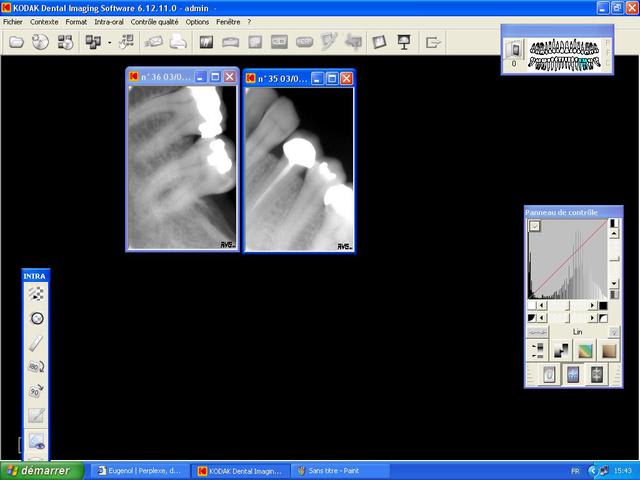

Voila les "retro-alveloaires"

Radio 36 35 37 iy6agl - Eugenol

entre temps s'il te plait apprends à centrer tes rétroalvéolaires.

les capteurs c'est super mais b....l mets un angulateur comme ça tu auras la couronne et l'apex .aucune des deux n'est "correcte" je sais ce n'est pas gentil mais tellement vrai.

au début on pensait faire réellement des "économies" d'exposition au patient en réduisant les doses mais on multiplie tellement les clichés car pas centrés etc... qu'au final c'est loin d'être le cas même avec la digue on arrive à centrer AVEC un angulateur , le doigt c'est fini depuis longtemps

Coucou, vi mes radios sont pas centrés, mais j'ai l'habitude de l'argentique sous angulateur.

La je travaille avec un enorme capteur RVG (au moins 8 mm d'épaisseur, donc j'y arrive pas :x) et il y a pas d'angulateur adapté. Toutes mes radios sont totalement merdiques, je te parle meme pas pour avoir les apexs de prémo-canines maxillaires..